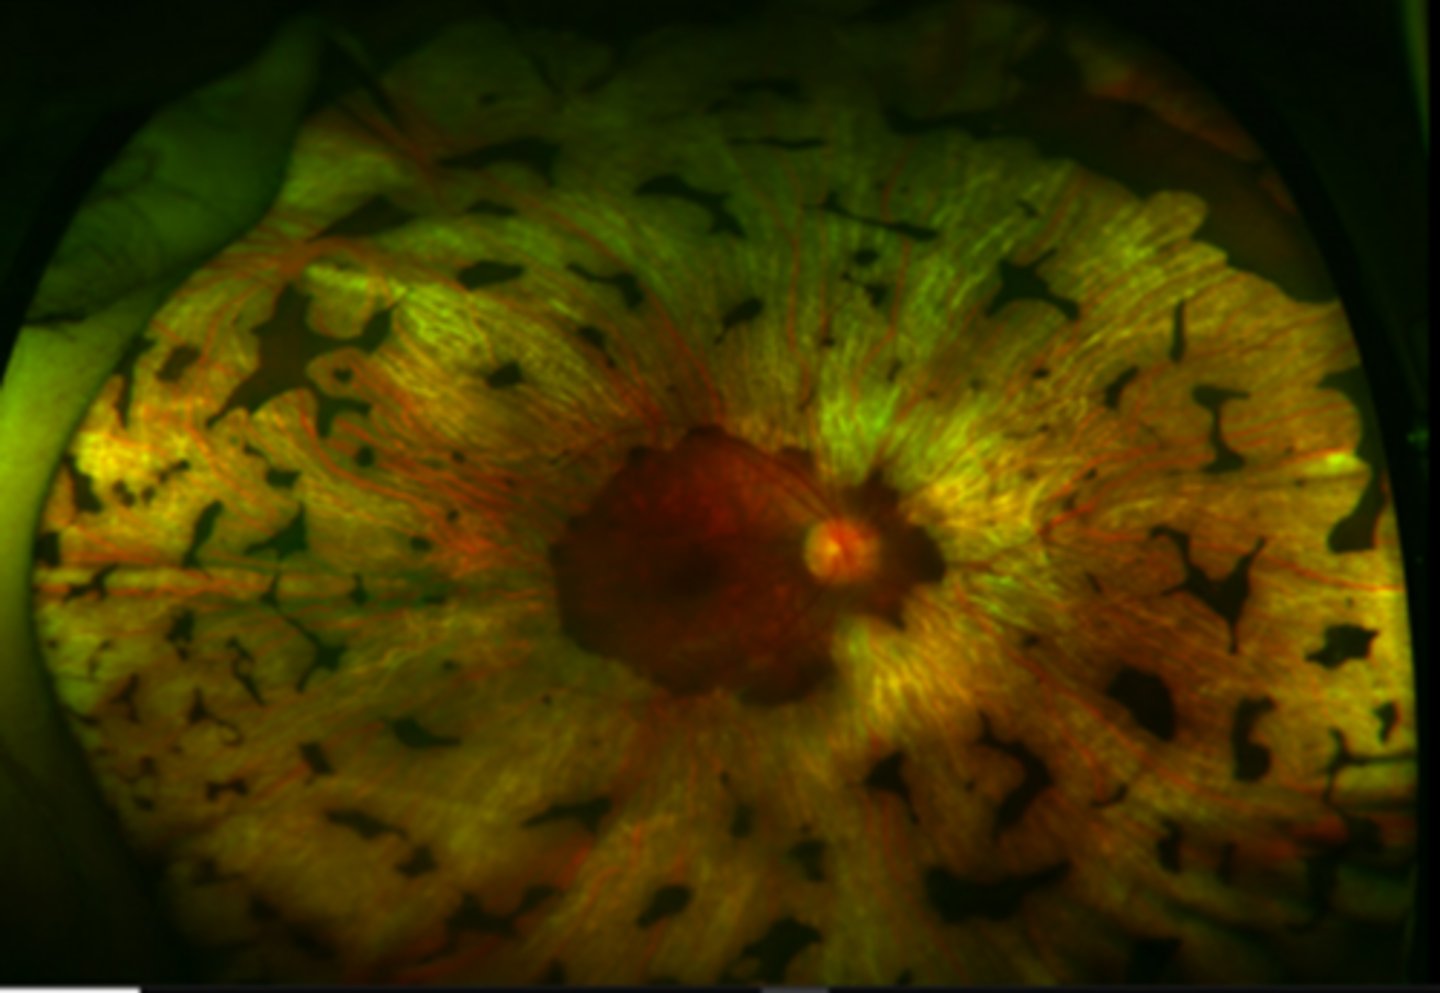

What findings of choroidemia are seen here?

scattered pigment clumping

visible large choroidal vessels

fovea = preserved choriocapillaris at the fovea

extrafovea = deficient choriocapillaris and visible medium, large choroidal vessels